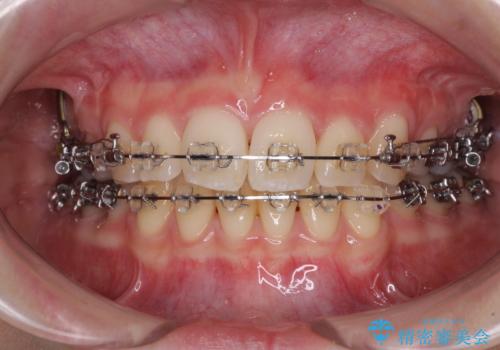

治療途中で転院 抜歯矯正の仕上げ治療

- 地元で抜歯治療を行っている途中、東京へ転職したため治療を継続して欲しいとのことで来院された患者様です。

出っ歯を抜歯矯正にて治療をしていらっしゃいましたが、抜歯スペースが少し残っていたため、閉じて歯列を仕上げていくこととしました。